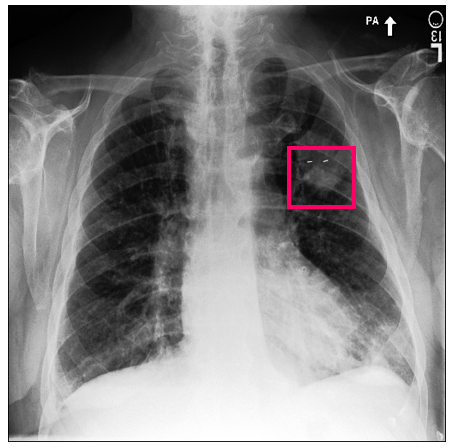

Refer to caption

(a) Ground Truth 1

(b) Ground Truth 2

(c) Ground Truth 3

(d) Ground Truth 4

(e) LIME 1

(f) LIME 2

(g) LIME 3

(h) LIME 4

(i) SHAP 1

(j) SHAP 2

(k) SHAP 3

(l) SHAP 4

Figure 10: Examples of LIME and SHAP explanations failing to capture the medical ground truth of a cancerous chest X-ray, while also generating conflicting explanations. Ground truth (a,b,c,d) is shown as red squares. Most important regions are bounded by yellow for LIME (e,f,g,h) and shown as more vibrant green for SHAP (i,j,k,l).